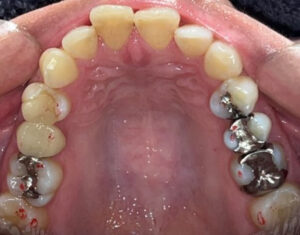

今回は、前歯のレイヤリングジルコニアセラミックの

治療をされた患者さまのご紹介です!

歯周治療、虫歯治療、審美治療の総合的な治療をおこないました。

修復の材料はほぼジルコニアセラミッククラウンで統一しています。

天然の歯は事前にホワイトニングを行い、全体的にトーンアップさせて、

それに合わせてカラーを決めています。

前歯のレイヤリングジルコニアはセラミストのデジタルトライインを行って

作製します!

全体的に綺麗になって患者さまもとても喜んでおられました♪